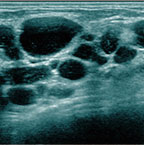

乳腺用エコー「エラストグラフィ」を使って以下のチェック項目でエコー検査を行います。

- しこりの原因

- しこりの位置

- しこりの状態

などを診ながら総合的な診断を行っていきます。しこりの状態やお悩みの状況に応じて、適切な治療法や解決法をご提案します。